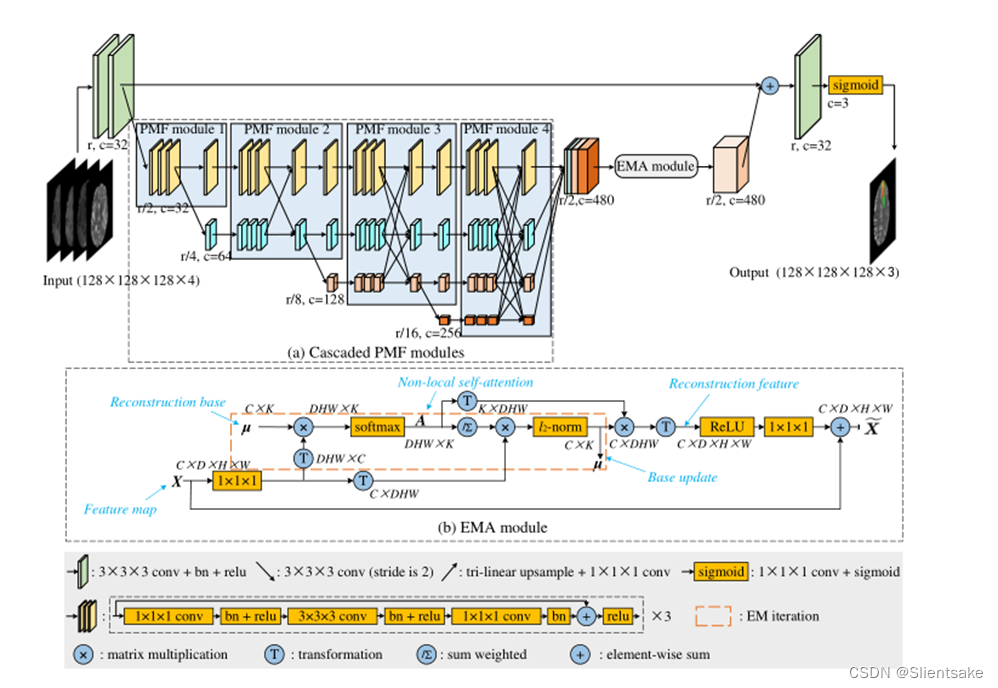

图2所示。原始HNF-Net的体系结构。在每一项研究中,四个多模态脑磁共振序列首先被连接起来形成一个四通道输入,然后在五个尺度上进行处理。R为原始分辨率,c为feature map的通道数。所有下采样操作都是通过2步卷积实现的,所有上采样操作都是通过关节1 × 1 × 1卷积和三线性插值实现的。需要注意的是,由于图中不方便显示4D特征图(C × D × H × W),所以作者将所有的特征图都显示出来,没有深度信息,每个特征图的厚度可以显示其通道号。

HNF-Net具有5个尺度的编解码器结构,如图2所示。在原始尺度r上,有四个卷积块,两个用于编码,另外两个用于解码。在其他四个尺度上,四个PMF模块被联合用作高分辨率和多尺度聚合特征提取器。在最后一个PMF模块的末尾,首先将四个尺度的输出特征映射恢复到1/2r尺度,然后将其拼接成混合特征。其次,利用EMA模块有效地捕获远程依赖上下文信息,并减少获得的混合特征的冗余。最后,EMA模块的输出通过1×1×1卷积和上采样恢复到原始比例r和32通道,然后添加到编码器生成的全分辨率特征图中,用于体素标签的密集预测。所有下样操作都通过2步卷积实现,所有上样操作都通过关节1 × 1 × 1卷积和三线性插值实现。

已经证明,学习强分辨率表示对于小目标分割任务至关重要,例如医学图像中的肿瘤和病变分割。在此基础上,采用多尺度卷积分支和全连接融合设置构建PMF模块,前者可以充分利用多分辨率特征,但保持高分辨率特征表示,后者可以聚合丰富的多尺度上下文信息。此外,作者在作者的HNF-Net中串联了多个PMF模块,其中分支的数量随深度递增,如图2(a)所示。因此,从最高分辨率阶段来看,通过多尺度低分辨率表示的反复融合,提高了其高分辨率特征表示。

非局部自注意机制虽然具有令人信服的从所有空间位置聚合上下文信息和捕获长期依赖关系的能力,但由于其潜在的高计算复杂度,难以应用于3D医学图像分割任务。为了解决这个问题,作者在作者的HNF-Net中引入了EMA模块,旨在将轻量级的非局部注意力机制纳入作者的模型中。EMA模块的主要概念(如图2 (b)所示)是在一组特征重建基础上操作非局部注意,而不是直接在高分辨率特征图上实现。由于重构基的元素比原始特征图少得多,可以显著降低非局部注意的计算成本。EMA模块的详细信息也可以在中找到。